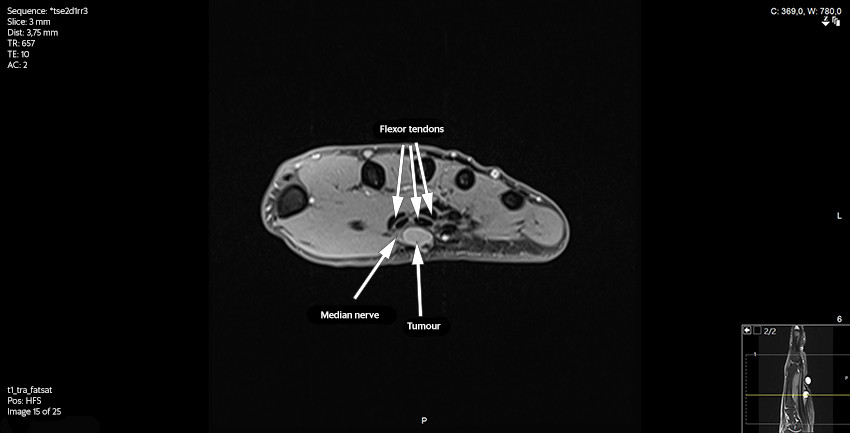

The patient was then referred for an MRI scan at a private clinic and subsequently to the orthopaedic department at the regional hospital. Following the MRI scan, the radiologist reported a contrast-enhancing, well-defined soft tissue tumour adjacent to or on the median nerve at the outlet of the carpal tunnel. It was concluded that the tumour was consistent with a schwannoma, but that another type of tumour could not be ruled out (Figures 2 and 3).